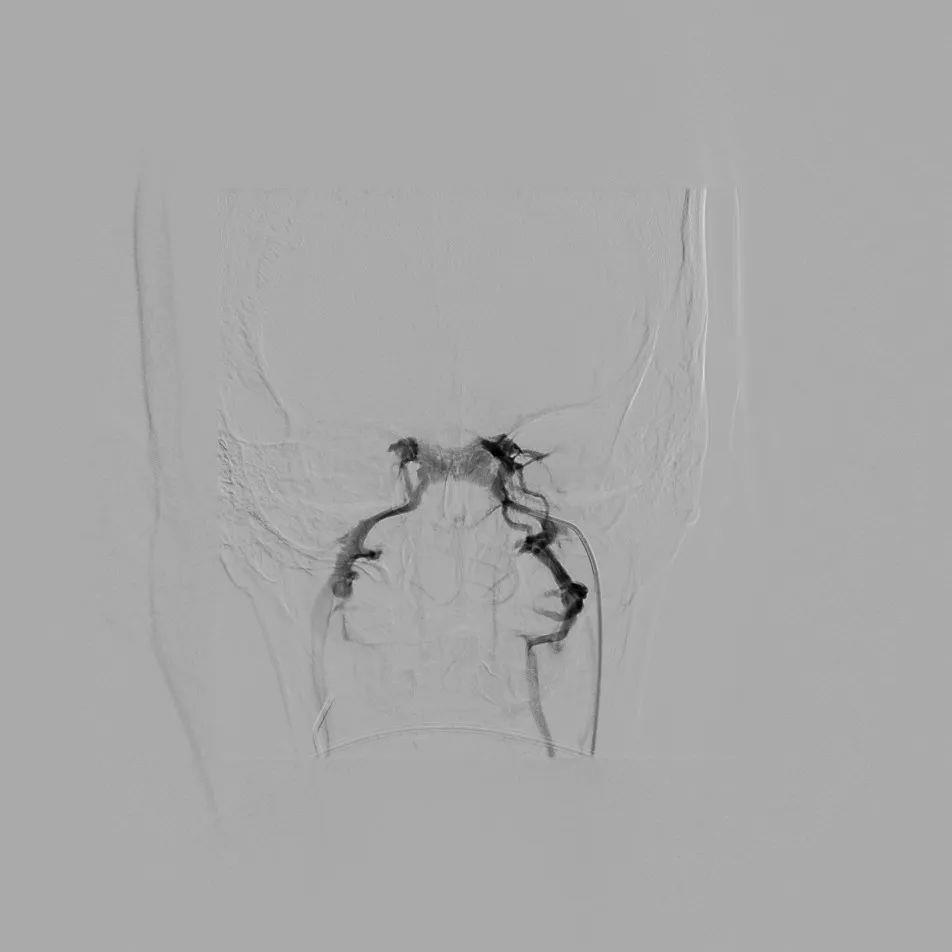

术中插管于双侧岩下窦静脉造影明确并采血

经微创介入团队实施岩下窦静脉采血术,采血结果经过检验提示为岩下窦静脉ACTH含量明显高于外周静脉血含量,明确为中枢性来源,遂转入神经外科行垂体瘤切除术。术后患者恢复良好,激素水平及皮质醇节律均恢复正常。

岩下窦位于颅底,周围毗邻重要血管和神经,同时岩下窦是垂体静脉回流的主要通道,直接收集垂体前叶分泌的ACTH,这为岩下窦静脉采血技术提供了解剖基础。岩下窦静脉采血通过股静脉入路,将导管经颈静脉至双侧岩下窦静脉同步采血,同时进行外周静脉采血,术后对岩下窦静脉血中ACTH含量与外周静脉血进行对比,判断ACTH分泌来源。